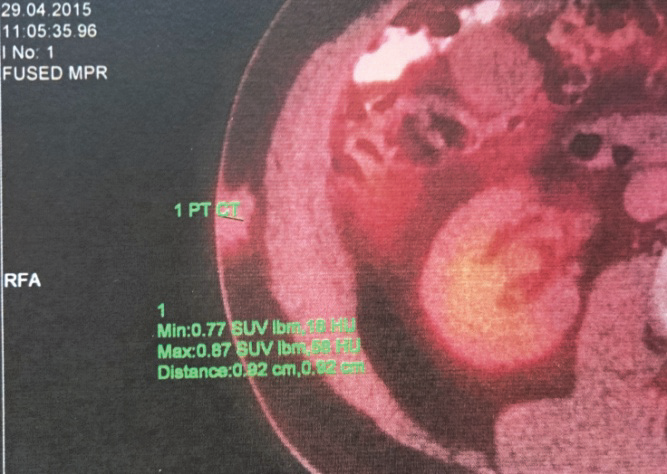

Totéž ložisko v podkoží na pravém boku dle hodnocení na PET-CT před zahájením léčby a 12 týdnů po zahájení léčby Vemurafenibem. Je patrné zmenšení ložiska a vymizení metabolické aktivity: